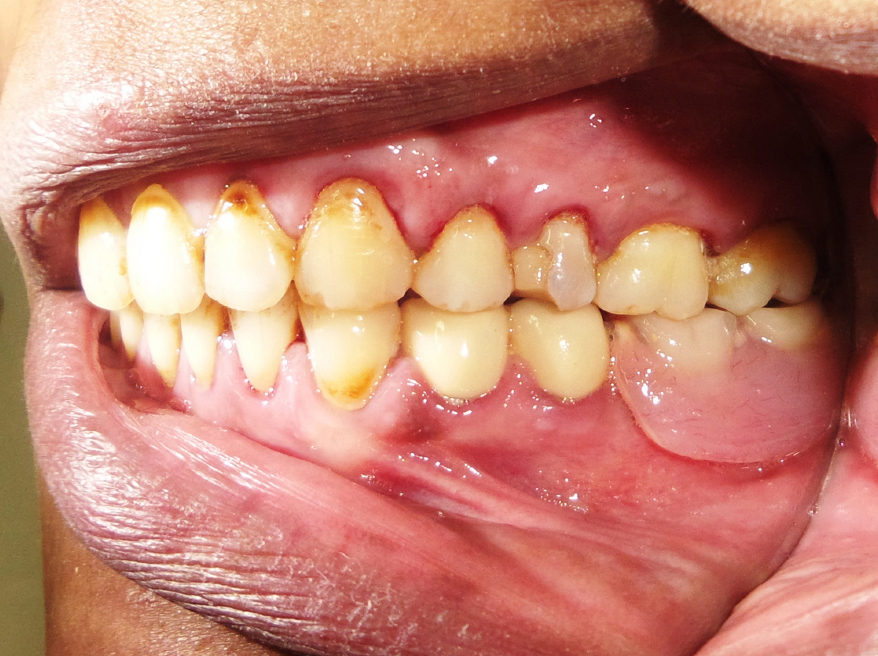

The framework was inserted in the patient's mouth and checked for accuracy and proper seating of crowns. The porcelain shade was then selected to match the remaining natural teeth. Then the porcelain was built on the splinted crowns. Semi–anatomical cross-linked acrylic teeth were set up, and the try-in was carried out. The saddle base was processed into heat cure acrylic resin, and the retentive nylon caps were inserted into the frame using the caps inserting tool. The splinted crowns-attachment assembly was finally cemented using Glassionmer cement (Fig. 6); the unilateral attachment prosthesis placement was then carried out (Fig. 7).

Fig. (6). Splinted crowns-attachment assembly was cemented.

Fig. (7). Attachmentretained partial denture.